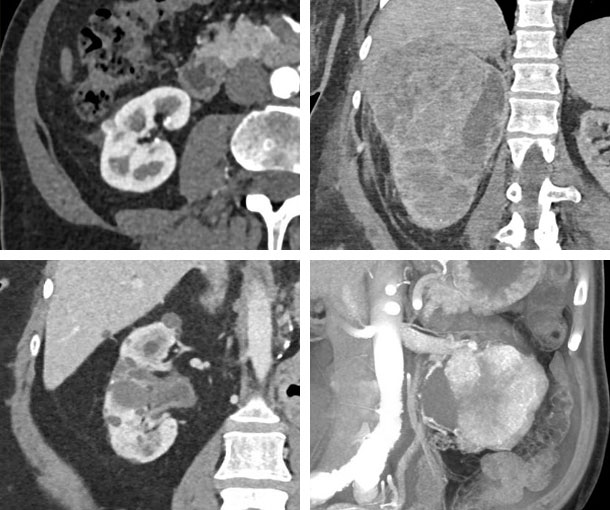

Renal Cell Carcinoma (RCC) CT Findings

- Solid or cystic mass

- RCCs may be isoattenuating, hypoattenuating, or hyperattenuating on non-contrast CT

- RCCs usually have decreased attenuation on contrast enhanced CT

- May have calcification